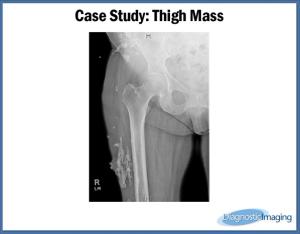

Thigh MassByChristal RobinsonAugust 18th 2015Case History: Woman in 7th decade of life presents with right lateral thigh mass.